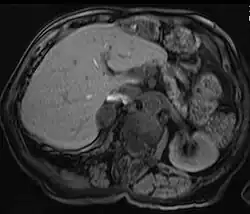

Adrenal adenoma in a patient with Conn syndrome

Due to their asymptomatic nature, most reported cases of adrenal adenomas have been discerned fortuitously through autopsy, or during medical imaging, particularly CT scan (computed tomography) and magnetic resonance imaging. Hence, they have earned the title incidentaloma referring to small adenoma discovered incidentally.[9] Though adrenocortical adenomas are considered challenging to differentiate from the normal adrenal cortex, they appear as well-circumscribed lesions once isolated.

Imaging Diagnostics

Adrenal-dedicated CT and MRI imaging can be performed to distinguish benign adenomas from potentially malignant lesions.[10] Online calculators assist radiologists in calculating the washout of contrast in adrenal nodules on CT[11] and chemical shift on MRI[12].